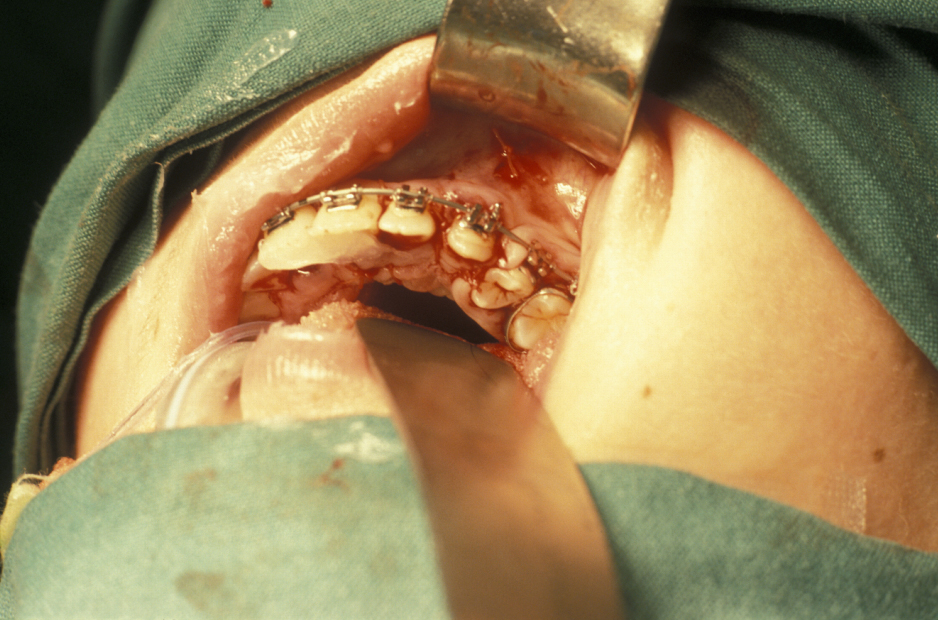

- Buccal Flap – a full thickness mucoperiosteal flap is raised from the buccal surface of the wisdom tooth area. The choice of incision varies, but commonly involves an incision along the external oblique ridge passing forward either around the second molar tooth or out into the buccal sulcus (Figure 3). If little or no bone is to be removed, a simple relieving incision may be all that is necessary. The important point is that dissection proceeds in a subperiosteal plane as this minimises postoperative swelling and trismus (Figure 4).

- Lingual Flap – some authorities do not raise a lingual flap at all. The popularity of this approach was from the days when accurate very high-speed surgical drills were not available and the ‘lingual split bone’ technique was popular in the UK and areas influenced by UK training. Their argument is that it is the process of actually raising the flap that causes injury to the lingual nerve. On the other hand, it is argued that the nerve is at risk from direct trauma from the burr/chisel if it is not retracted. Again, if used, the flap is raised by subperiosteal dissection. Here it is important not to ‘bow-string’ the nerve over the retractor (usually a Howarth’s elevator; Figure 1), but to widely undermine the lingual periosteum to allow the tissues to lie passively and use a wide subperiosteally placed retractor. The elevation of a small cuff of distal attached mucosa is designed for visibility, not for ‘lingual nerve protection’ and is not associated with an increase in morbidity (Figure 5).